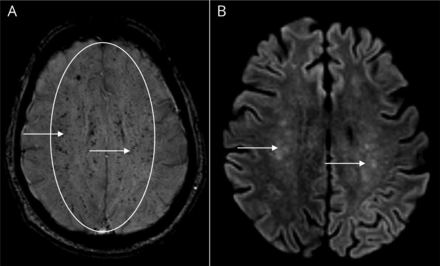

(一)瑞士核桃仁的皮质下区域中的多个hypointensities模式。(B)与星际模式多种hyperintense醉酒驾车,片状双边深度和皮层下白质病变。醉酒驾车= diffusion-weighted成像;瑞士= susceptibility-weighted成像。

涉及多个血管领土的出血性中风的鉴别诊断包括外伤、脑淀粉样血管病,可逆的大脑血管收缩综合症,转移性肿瘤、脓肿和中枢神经系统或全身性感染,如心内膜炎、血管炎、凝血障碍。MRI大脑有或没有对比显示异常T2 fluid-attenuated反转恢复hyperintensity线性和结节性增强和广泛的瑞士hypointensities涉及放射冠、胼胝体、室周的白质,基底神经节,脑干和小脑展示microhemorrhages符合“核桃仁”模式和扩散限制在双边深度和皮层下白质符合“星际”模式(图)。这种模式提出脑脂肪栓塞(CFE)。

我们的Hb SC患者疾病经验丰富的急性神经认知疾患危机后下降。我们的病人的演讲是很重要的两个原因。首先,这可能是唯一的诊断报告无着丝粒的缄默症造成CFE设置的严重的神经损伤,如核磁共振。1CFE的重要影像学表现包括星际模式对醉酒驾车和核桃仁模式在瑞士。8,9第二,延迟诊断导致延迟交换输血。6,7使人放心GRE序列初始MRI大脑可能导致延迟。10瑞士序列可能是有助于作出早期诊断,因为它可能优于GRE序列检测microhemorrhages,这通常发生在《。11